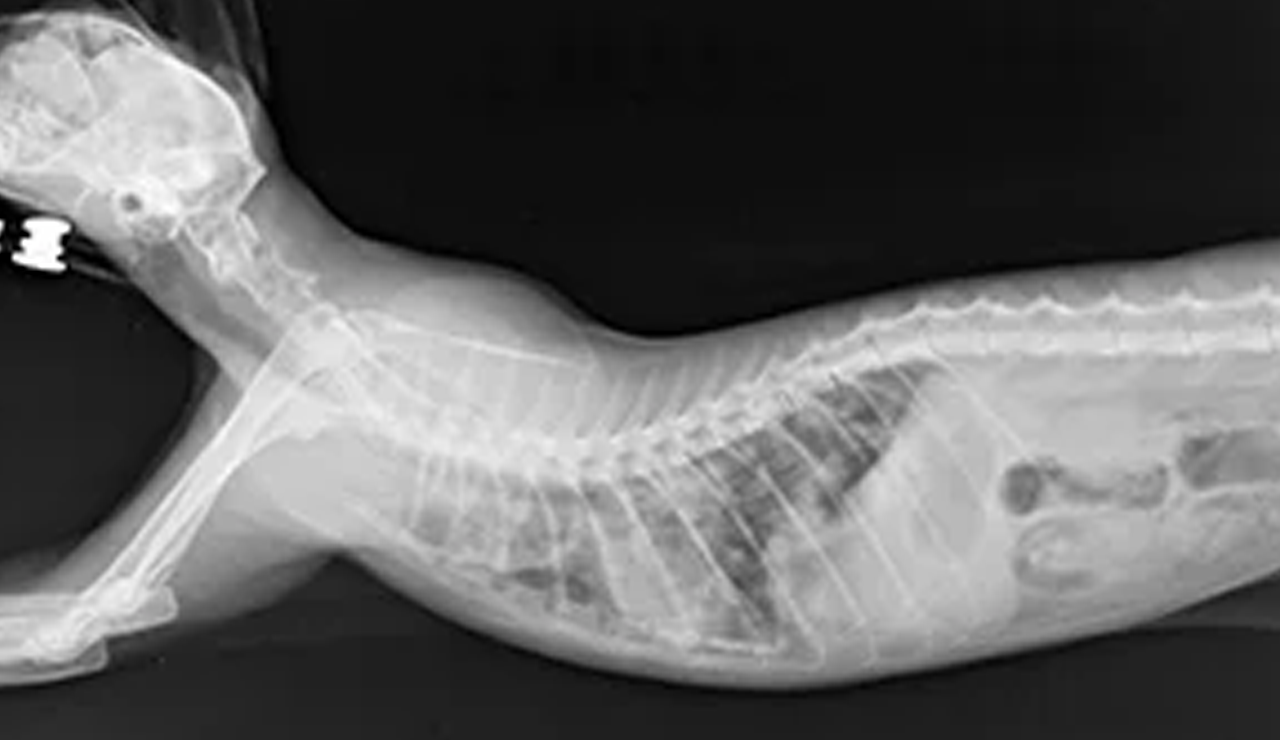

レントゲン検査装置 |

| X線の透過により、全身の骨、関節、肺、心臓、内臓の位置や形について異常を検出する装置。呼吸器疾患や整形疾患では特に重要な検査となります。 |